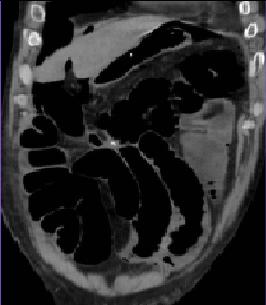

La CT scanner coronale

y avait le role importante dans diagnostic des

occlusion intestinale aigue :Y avait il de occlusion ? , la degree de occlusion ,

la situation de obstacle , la cause et les complications .

Aspect radiologique TDM de occclusion de l'intestin

grele est : |